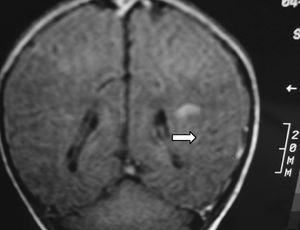

A los 4 meses de vida se constató una hemiparesia derecha por lo que se realizó RM cerebral, presentando atrofia de la mayor parte del lóbulo parietal izquierdo y del tálamo del mismo lado con múltiples cavidades porencefálicas en el territorio de la arteria cerebral media izquierda. Se observaba así mismo un ensanchamiento del ventrículo lateral derecho (figs. 4 y 5). La angio-RM está pendiente de realización.

Figura 5.Flair coronal: hemiatrofia izquierda con múltiples cavidades porencefálicas en el territorio de la ACM izquierda.